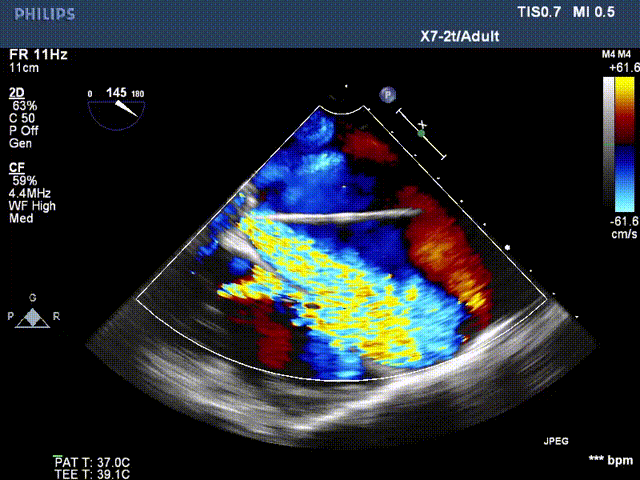

超声检查

患者二尖瓣机械瓣瓣周可见两处间隙,分别位于10点位、1-2点位,大小分别约为:10点位7×5mm,1-2点位10×4mm,彩色血流提示二尖瓣位瓣周返流(两束,大量),主动脉瓣位机械瓣上血流速度正常,瓣周未见明显返流。

心脏超声可见两处二尖瓣瓣周漏